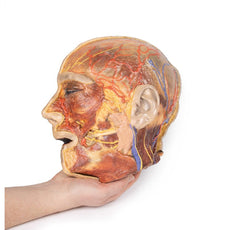

The head and neck of the specimen provides views of both superficial and deep structures in the region. The calotte has been removed ~2cm superior to the orbits to expose the brain in relation to the endocranial cavity. The transverse section through the cerebrum demonstrates the relation of the grey matter cortex to the white matter medulla, as well as the lateral ventricles with a small amount of choroid plexus visible in the base of both spaces. The skin and superficial fascia on the right side has been retained and false-coloured to display the angiosomes of the face and posterior neck. On the left side, the superficial tissues have been dissected to expose the muscles of facial expression, muscles of mastication, and deeper structures of the infratemporal fossa including the lingual nerve, terminal branches of the external carotid artery into the superficial temporal and maxillary arteries.

The carotid sheath has been opened on both sides of the neck, and the internal jugular veins and sternocleidomastoid muscles largely removed, to expose the pathway of the common carotid arteries, internal and external carotid arteries, and the vagus nerves. On the right side, the great auricular nerve ascends towards the face, while the hypoglossal nerve can be seen adjacent to the exposed stylohyoid ligament and supra- and infrahyoid muscles. A large thyroid gland is present bilaterally inferior to the thyroid cartilage, with a well-preserved superior thyroid artery and inferior thyroid vein on the right side and across the midline.

The head and neck of the specimen provides views of both superficial and deep structures in the region. The calotte has been removed ~2cm superior to the orbits to expose the brain in relation to the endocranial cavity. The transverse section through the cerebrum demonstrates the relation of the grey matter cortex to the white matter medulla, as well as the lateral ventricles with a small amount of choroid plexus visible in the base of both spaces. The skin and superficial fascia on the right side has been retained and false-coloured to display the angiosomes of the face and posterior neck. On the left side, the superficial tissues have been dissected to expose the muscles of facial expression, muscles of mastication, and deeper structures of the infratemporal fossa including the lingual nerve, terminal branches of the external carotid artery into the superficial temporal and maxillary arteries.

The carotid sheath has been opened on both sides of the neck, and the internal jugular veins and sternocleidomastoid muscles largely removed, to expose the pathway of the common carotid arteries, internal and external carotid arteries, and the vagus nerves. On the right side, the great auricular nerve ascends towards the face, while the hypoglossal nerve can be seen adjacent to the exposed stylohyoid ligament and supra- and infrahyoid muscles. A large thyroid gland is present bilaterally inferior to the thyroid cartilage, with a well-preserved superior thyroid artery and inferior thyroid vein on the right side and across the midline.